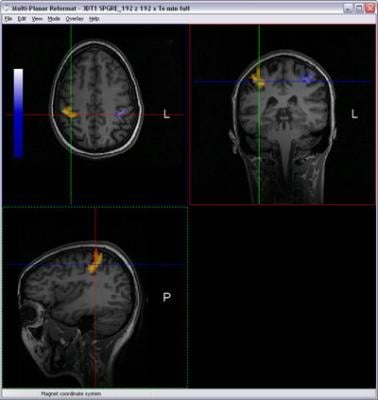

December 9, 2008 – The FDA issued 510(k) approval for market clearance of nordicICE BOLD and DTI Modules developed by NordicNeuroLab (NNL), applications optimizing workflow associated with analyzing and combining Diffusion Tensor Imaging and BOLD fMRI data.

One of the new features in nordicICE v2.3 is the BOLD and DTI Wizard - dedicated to simplifying and optimizing the workflow associated with analyzing and combining Diffusion Tensor Imaging and BOLD fMRI data. This wizard provides an intuitive and easy-to-use step-by-step interface that guides the user through the process of loading, analyzing and visualizing multimodality imaging data. The new integrated Multi-Planar Reconstruction and 3D visualization interface offers unique tools for combining functional activation maps and white matter fiber tracts on a structural image volume. The resulting datasets (both fiber structures and activation maps) can be readily exported to various neuronavigation and treatment planning systems.